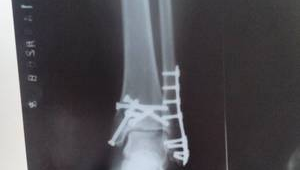

随着时间的推移,当骨折部位逐渐愈合,通过影像学检查确认骨折线模糊或消失后,患者可以在医生的指导下逐渐增加活动量。即使骨折已经基本愈合,脚踝放了钢板后仍存在一些潜在的风险因素。钢板作为一种异物植入体内,可能会对脚踝的灵活性和稳定性产生一定影响。在踢足球这种需要频繁变向、急停、跳跃的运动中,脚踝所承受的压力和冲击力较大,这可能会增加再次受伤的几率。

不过,这并不意味着脚踝放了钢板后就绝对不能踢足球。一些患者在经过长时间的康复训练,并且身体状况达到较好水平后,是可以尝试参与一些相对温和的足球活动的。比如,可以先从一些简单的传球、短距离带球练习开始,逐渐适应运动的节奏和强度。在运动过程中,要佩戴好合适的护具,如护踝等,以提供额外的支撑和保护。